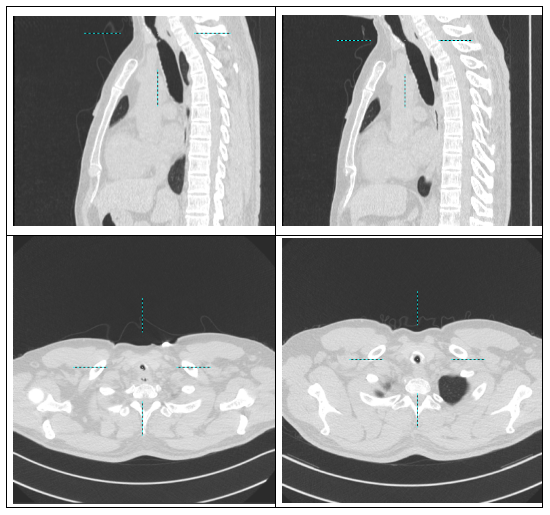

经检查确诊:气管上段严重瘢痕+肉芽增生性狭窄,长度约3cm,管腔扭曲,多次球囊扩张后易回弹,常规治疗难以维持气道通畅。

手术定位精准、出血少,气道瞬间恢复通畅,通气功能即刻改善。

复查显示:支架位置良好、固定稳妥,气道通畅无阻,患者顺利康复出院。